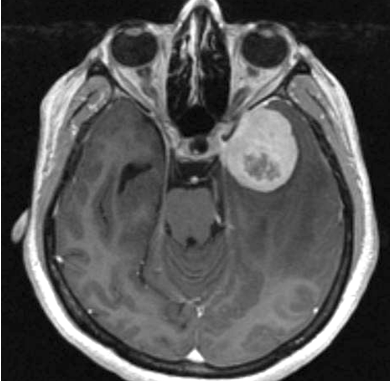

Photo Courtesy of Mayo Clinic

Clinicians typically classify meningiomas — the most common type of brain tumor — into three grades, ranging from slow-growing to aggressive. But a new multi-institutional study suggests that appearances may be deceiving. If a tumor shows activity in a gene called telomerase reverse transcriptase (TERT), it tends to recur more quickly, even if it looks low-grade under the microscope.

Meningiomas — tumors of the meninges, the protective tissue that surrounds the brain and spinal cord — are generally considered benign. But a small subset of these tumors has a mutation in the TERT gene, which is linked to faster growth and a shorter time before the tumor returns after treatment.